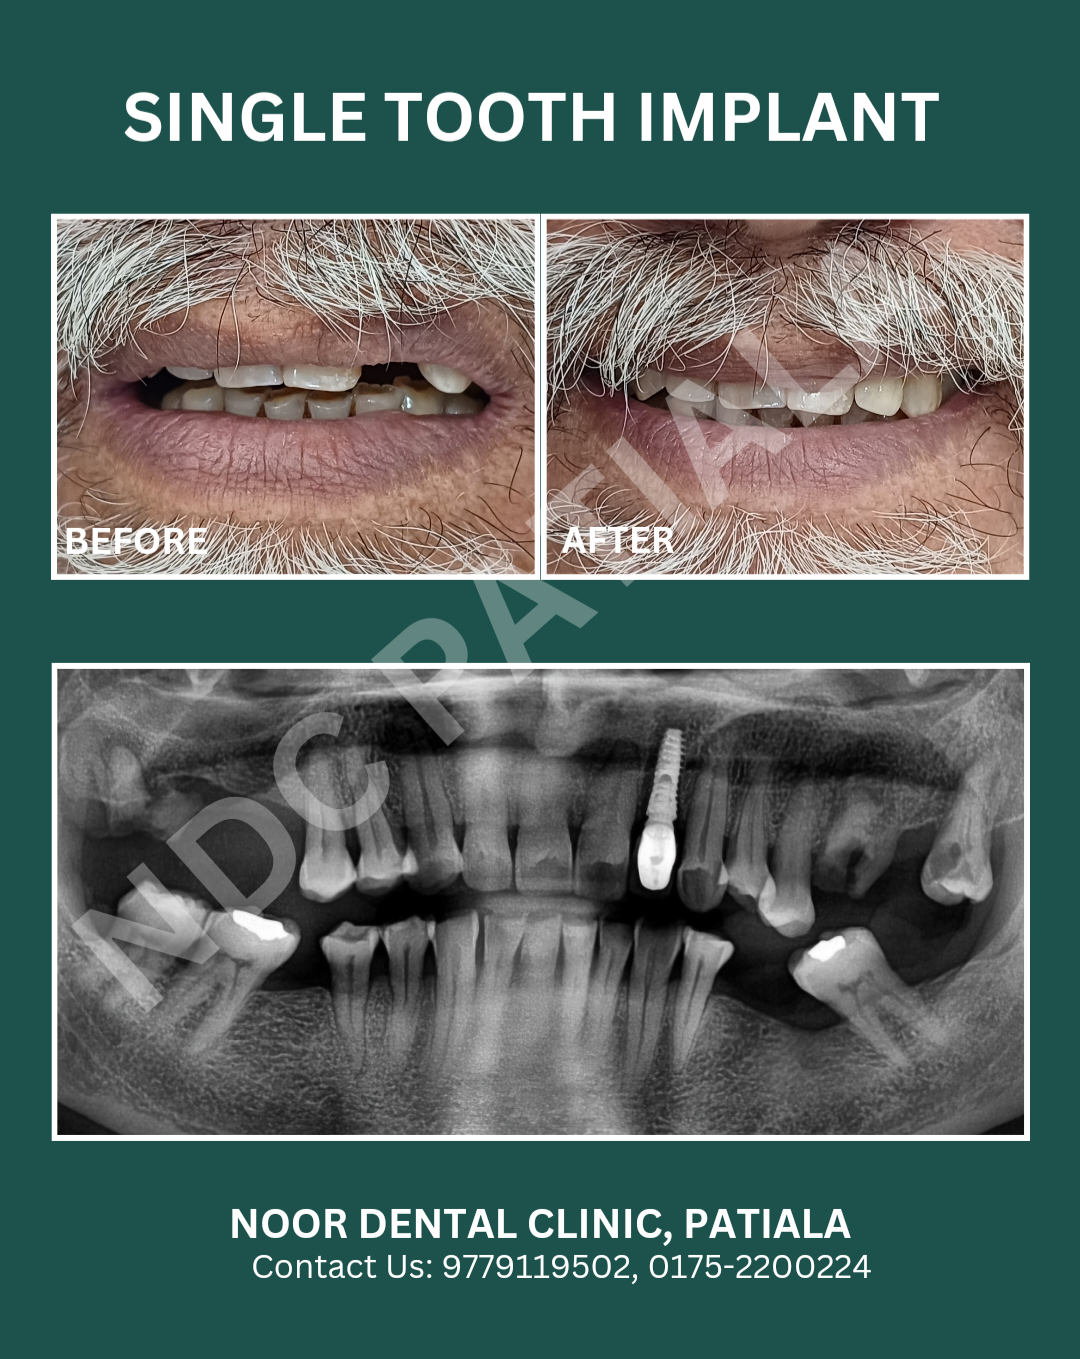

Dental Implants

Featured Work